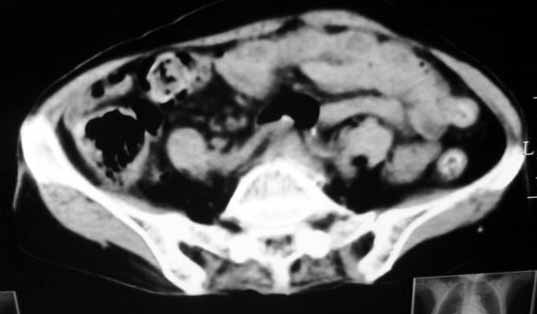

3.右肾前外极囊性低密度影,边界清楚,考虑肾囊肿可能。

2、右肾上极小囊肿;

3、脾门区淋巴结钙化。

腹膜后占位性病变,腹膜后淋巴结转移,脾门动脉硬化,右肾囊肿。